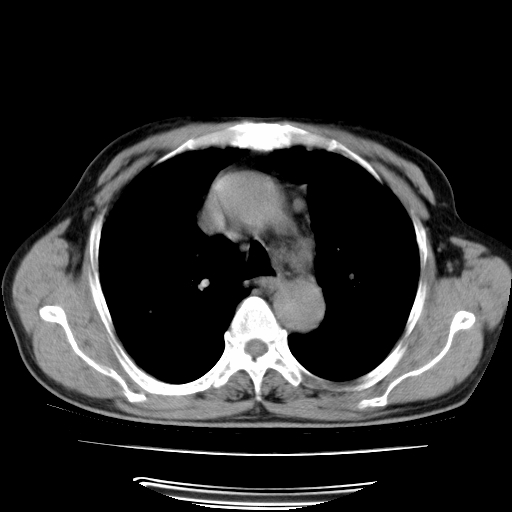

男,71岁,咳嗽,气喘10年,再发并咯血.胸片见气胸

考虑  左肺中心型肺癌伴阻塞性肺炎,肺不张,纵膈淋巴结肿大。慢支炎,肺气肿,左侧气胸肺压缩5%

左侧中央型肺癌伴纵膈淋巴结转移。

左肺中心型肺癌伴阻塞性肺炎,肺不张,纵膈淋巴结肿大

1)考虑左肺中心型肺癌伴阻塞性肺炎、左肺下叶肺不张、左侧肺气肿,纵膈淋巴结转移。2)左侧气胸(肺组织压缩约5%)。

左肺中心型肺癌伴阻塞性肺不张、肺气肿 。

1)考虑左肺中心型肺癌伴阻塞性肺炎、左肺下叶肺不张、左侧肺气肿,纵膈淋巴结转移。2)左侧气胸。